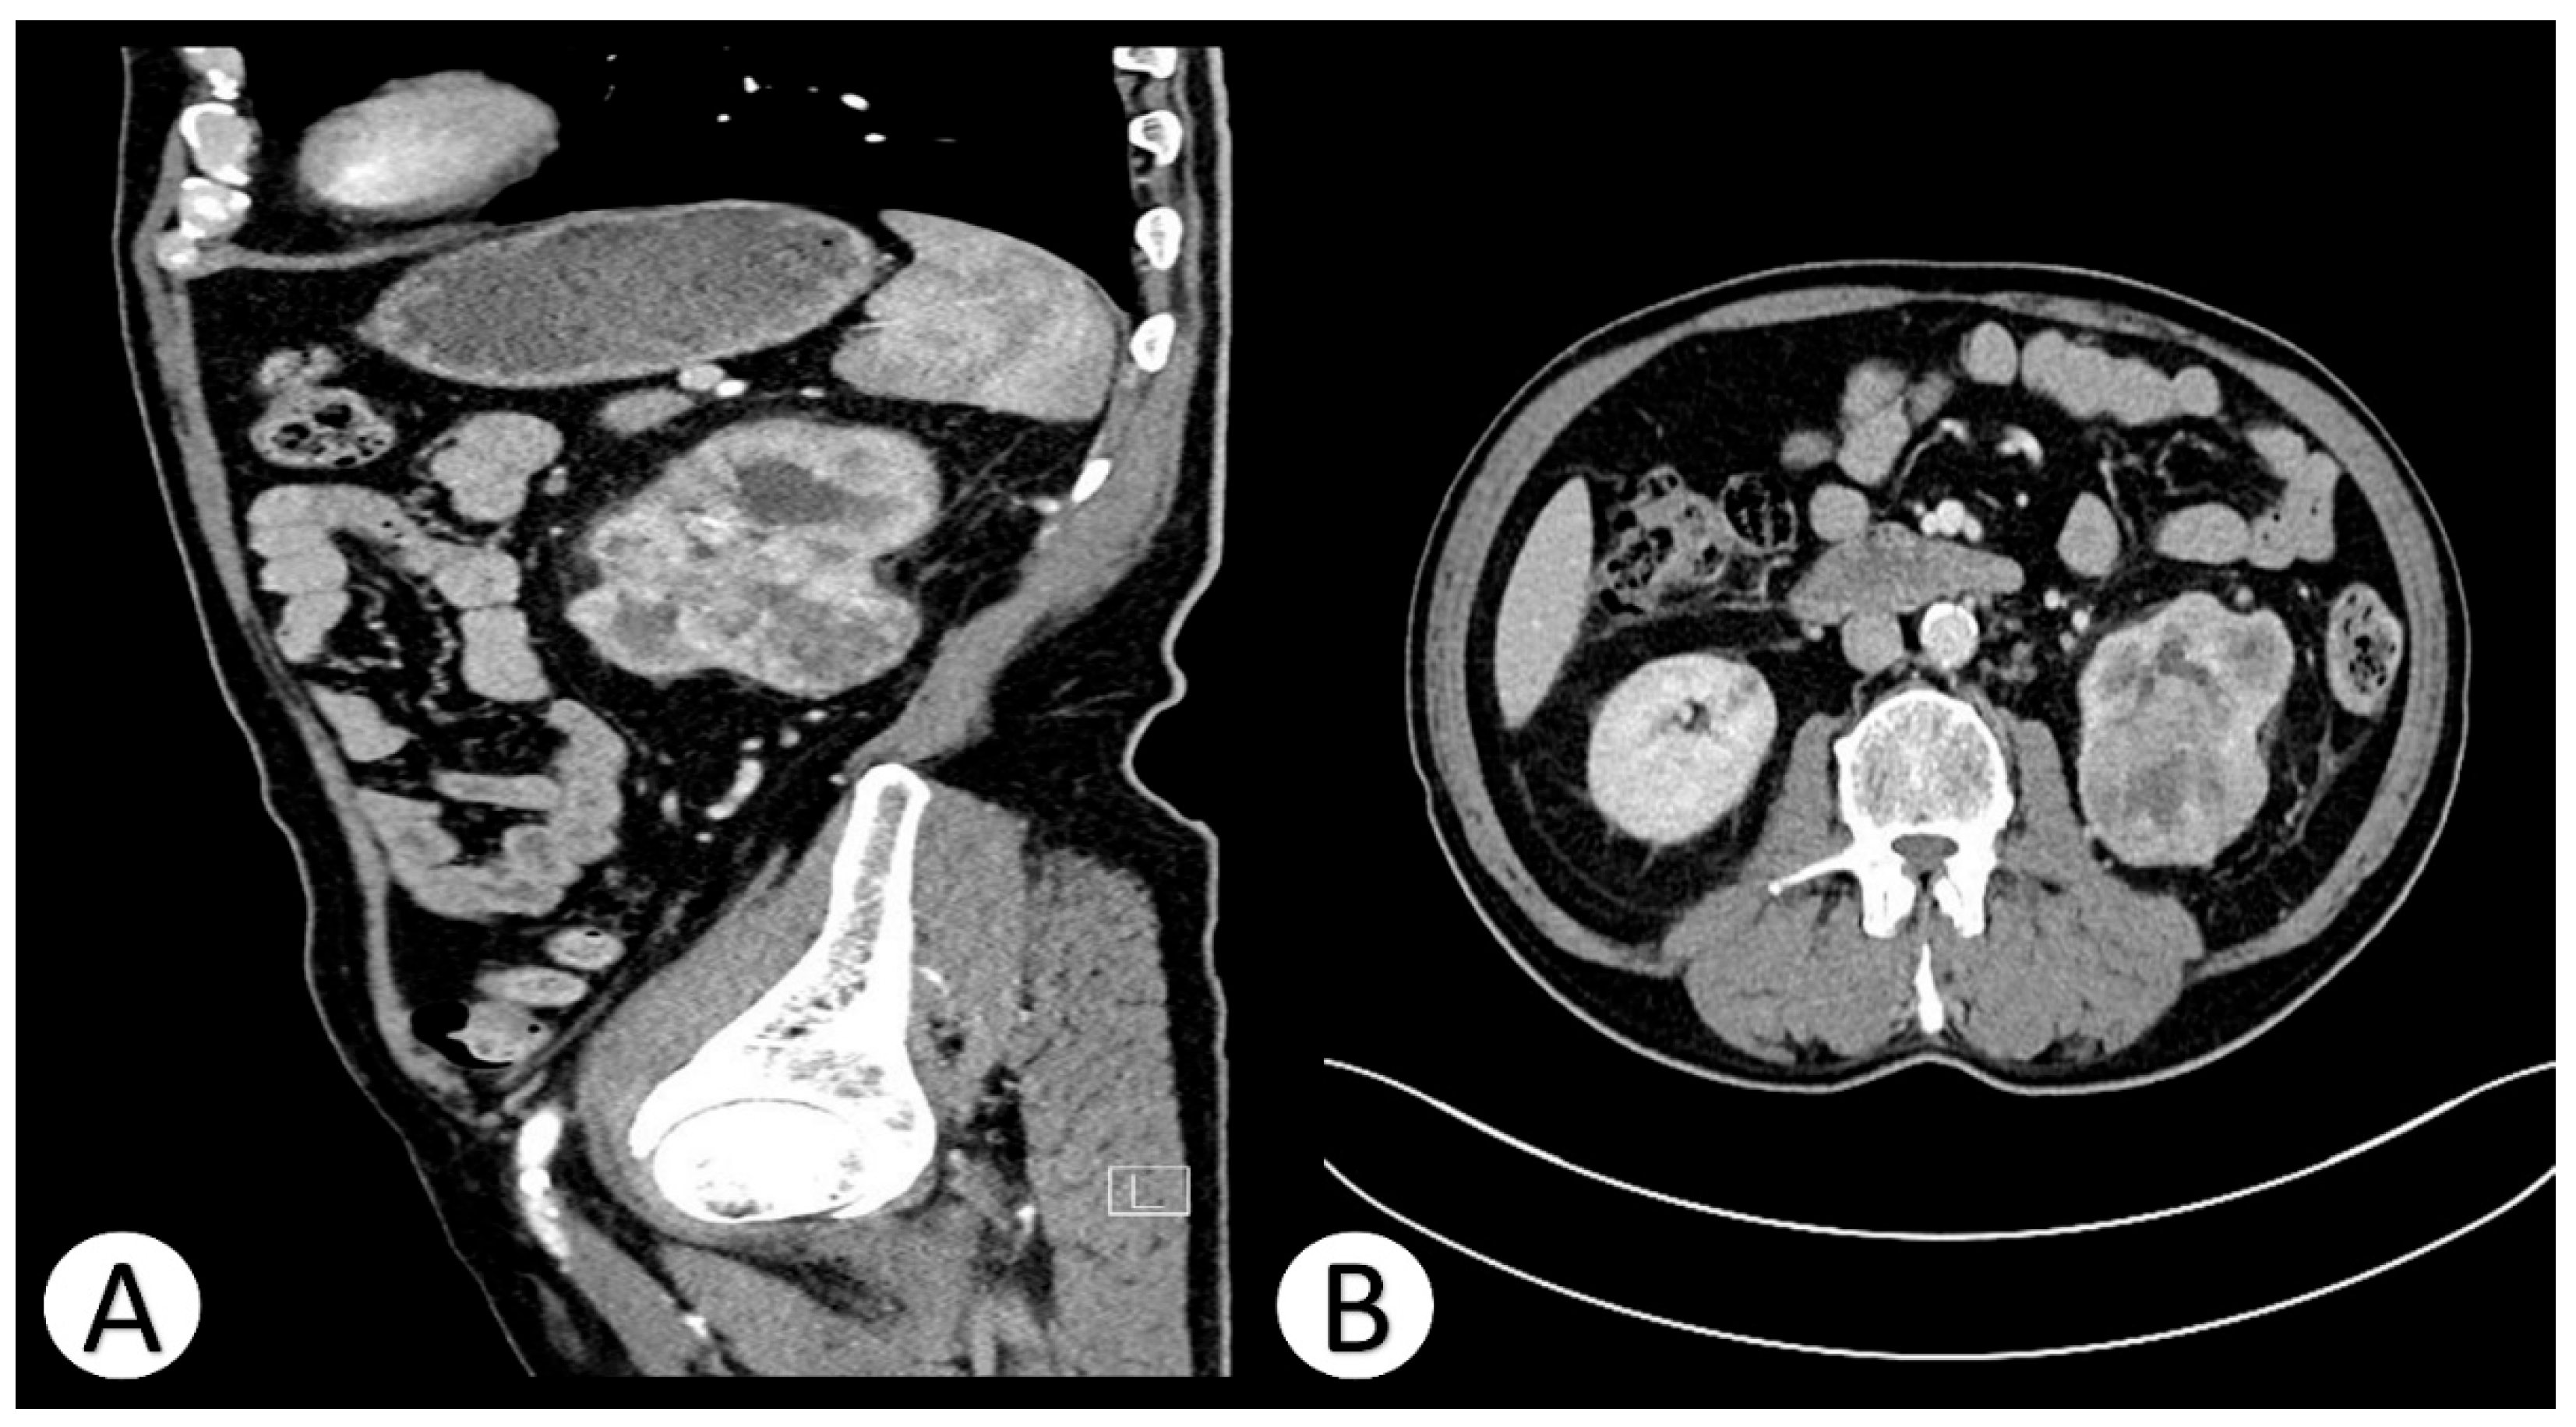

Contrast-enhanced computed tomography (CT) of the abdomen revealed a large (51 × 61 × 52 mm), heterogeneous, well-circumscribed mass originating from the mid to lower pole of the left kidney. The lesion exhibited mixed density with solid and necrotic components and heterogeneous contrast enhancement, consistent with a hypervascular renal tumor. Multiple bilateral pulmonary nodules (up to 24 mm) were also identified, highly suspicious for metastatic deposits. Additionally, para-aortic and paracaval lymphadenopathy (up to 18 mm) was visualized (

Figure 1).